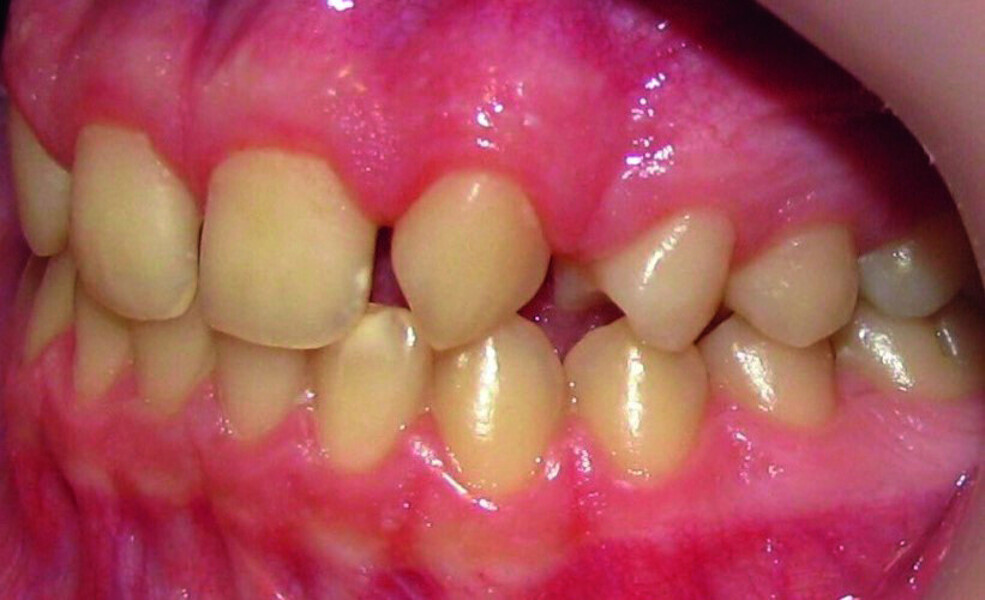

Orthodontic management of maxillary lateral incisors agenesis